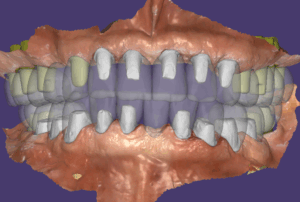

이렇게 해서 전체적이 치료가 예쁘게 튼튼하게 잘 마무리가 되었습니다. 전체임플란트 치료를 수십년간 수천명을 치료하면서 점점 치료가 발전하고 있어요. 지금의 치료법까지 오는 길이 쉽지는 않았지만 그 길을 찾아오는 여정이 흥미롭고 행복했습니다.

임플란트 보철 속에 이런 식으로 지대주가 들어있어요.

이 분은 잇몸질환으로 치아를 뽑지 않았기 때문에 비교적 뼈의 모양이 잘 유지되어 있어서 결과가 더 예쁜 것 같아요.

이 분은 수술하신 지 4년 정도 되셨고 치료완료후 미국에서 관리하시다가 올해 한 번 검진 오셨는데 상태 아주 좋았습니다. 계속 잘 사용하시길 바라는 마음입니다.